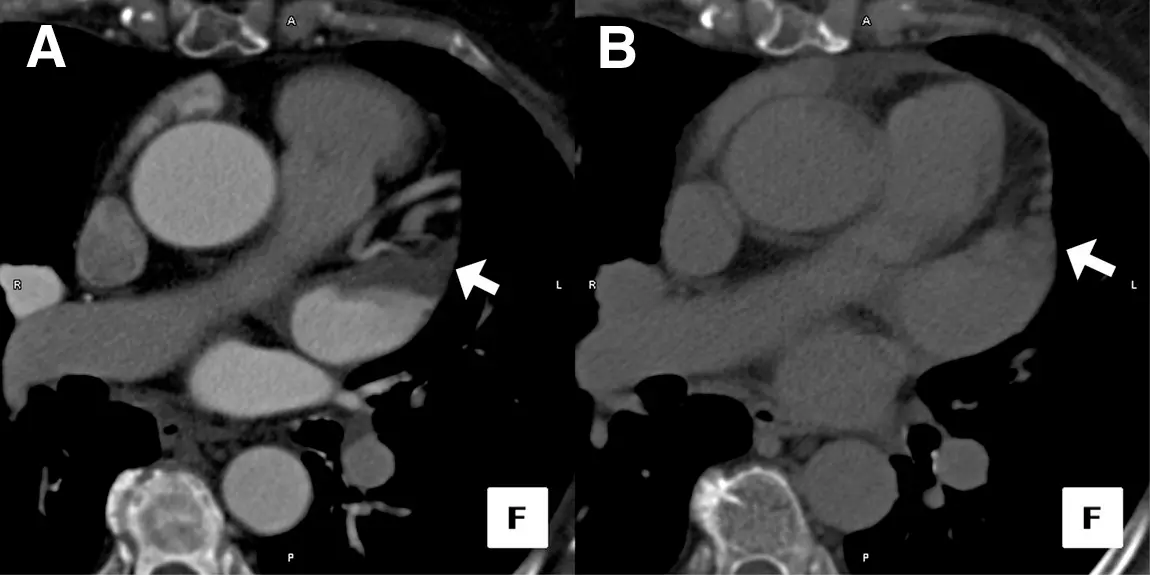

Figure source: 2 - Axial image of a Cardiac CT Study Performed in a Patient Before RF Pulmonary Vein Ablation: (A) Initial image obtained after contrast injection demonstrates filling defect in the left atrial appendage tip. (B) Delayed image obtained 1 min after initial scan shows homogeneous opacification, suggesting an absence of thrombus.